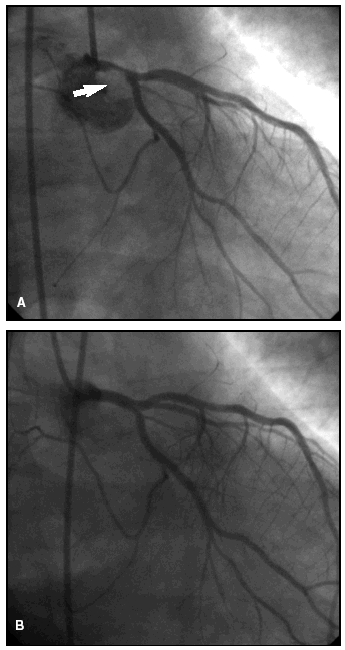

La estenosis era significativa (superior al 50%) en todos los casos. La localización fue proximal en 3 pacientes (casos 1, 5 y 6), con inclusión del ostio en 2, distal en 2 (casos 2 y 3) y tubular en uno (caso 4). La lesión se extendía en una longitud de 5-12 mm con una morfología excéntrica e irregular siempre, calcificada en 3 casos y con imagen de trombo agudo en 2 (fig. 2). Tres pacientes tenían lesiones significativas (≥ 75%) en otras arterias coronarias: uno en la derecha (ACD) media, uno en la descendente anterior (ADA) media y el otro en la ACD proximal y la ADA media. Un paciente (caso 6) tuvo una fibrilación ventricular durante el procedimiento, por lo que hubo que continuarlo con un balón de contrapulsación intraaórtico.

Figura 2. Coronariografía (paciente n.º 2) en la cual se observa (A) una estenosis significativa del tronco común de la arteria coronaria izquierda (flecha), ulcerada con trombo, con buenos lechos distales, resuelta (B) tras angioplastia e implante de stent.